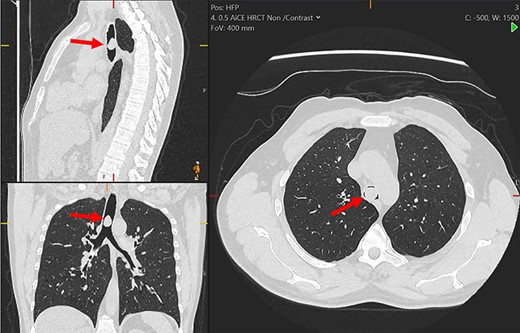

Multiplanar reformation of the chest computerized tomography demonstrating the tracheal mass (red arrows).

On examination, he had normal chest expansion and no hyperinflation. Expiration was not prolonged and there was no expiratory wheeze or inspiratory stridor. Repeat spirometry revealed FEV1 = 0.98 l (predicted 3.90 l) and FVC = 5.10 l (predicted 4.84 l) with an expiratory flow-volume loop demonstrating pressure-dependent collapse and a clipped inspiratory loop, which suggested upper airway obstruction (Fig. 1A and B). The patient was referred for a computed tomography chest which revealed a 2.3 cm × 1.5 cm polypoid mass arising from the posterior aspect of the trachea approximately 2 cm above the carina (Fig. 2). Bronchoscopy was performed and the mass resected using Nd:YAG laser (Fig. 3A–D). The lesion was wide-based arising from the trachealis muscle mucosa. The patient was discharged the same day. Histological analysis revealed a spindle cell lesion with a fascicular arrangement suggesting smooth muscle differentiation without malignant features (Fig. 4A–D). Immunohistochemistry confirmed the expression of smooth muscle actin, desmin and H-caldesmon, in keeping with leiomyoma. Follow-up at 6 weeks revealed complete resolution of symptoms. Repeat spirometry demonstrated FEV1 = 3.56 and FVC = 4.94 and the flow-volume loop had normalized (Fig. 5).